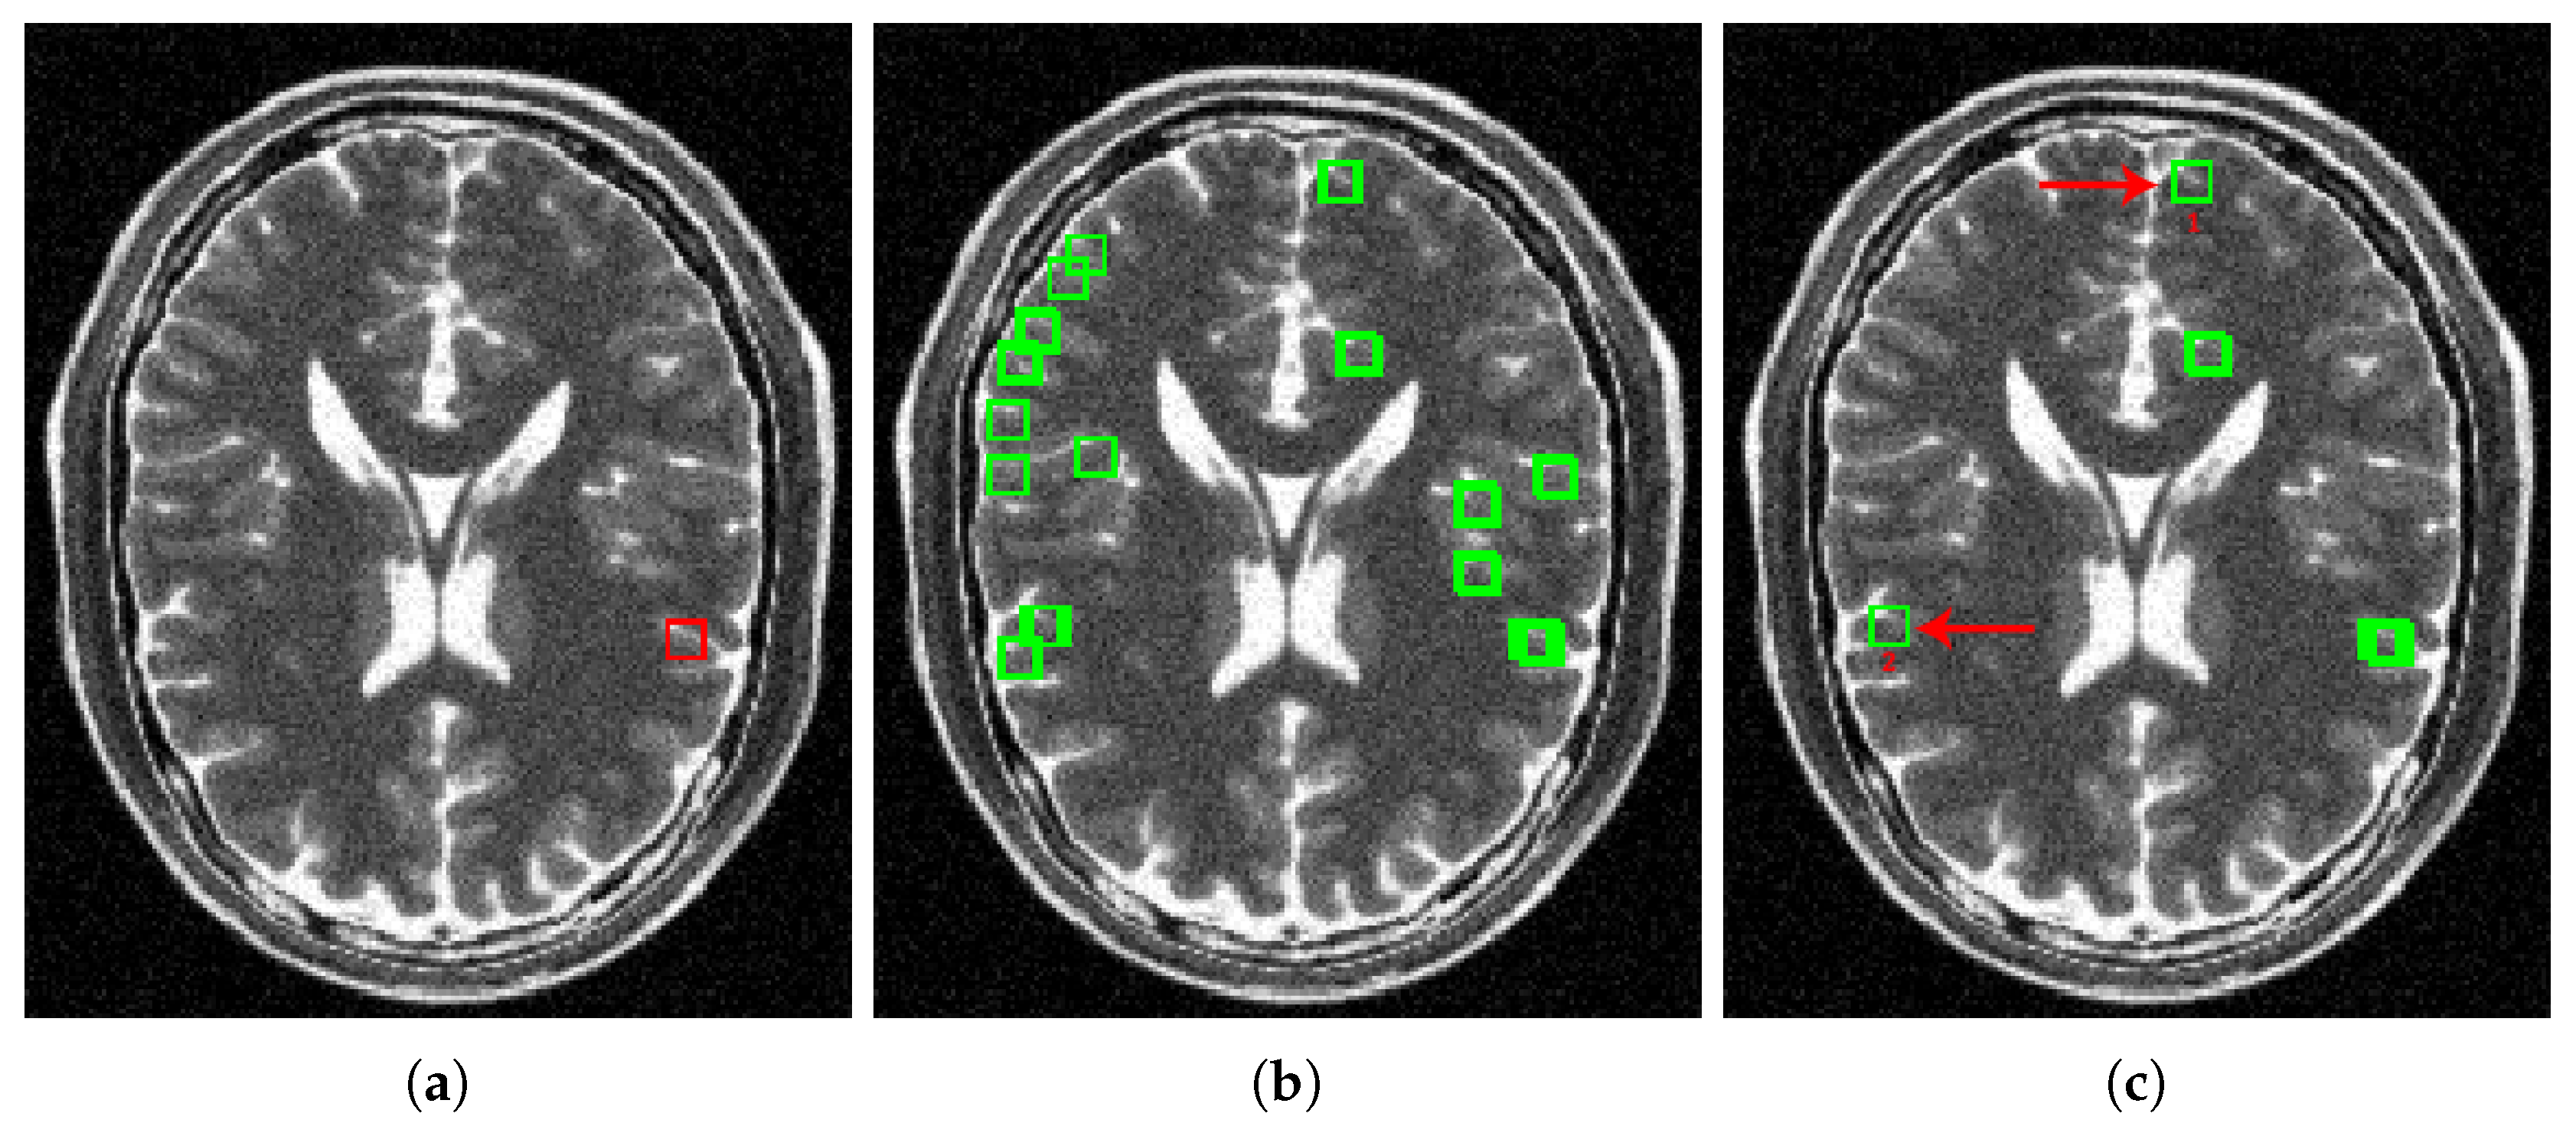

3.2.1. Signal Grouping

4.2.2. Real Data